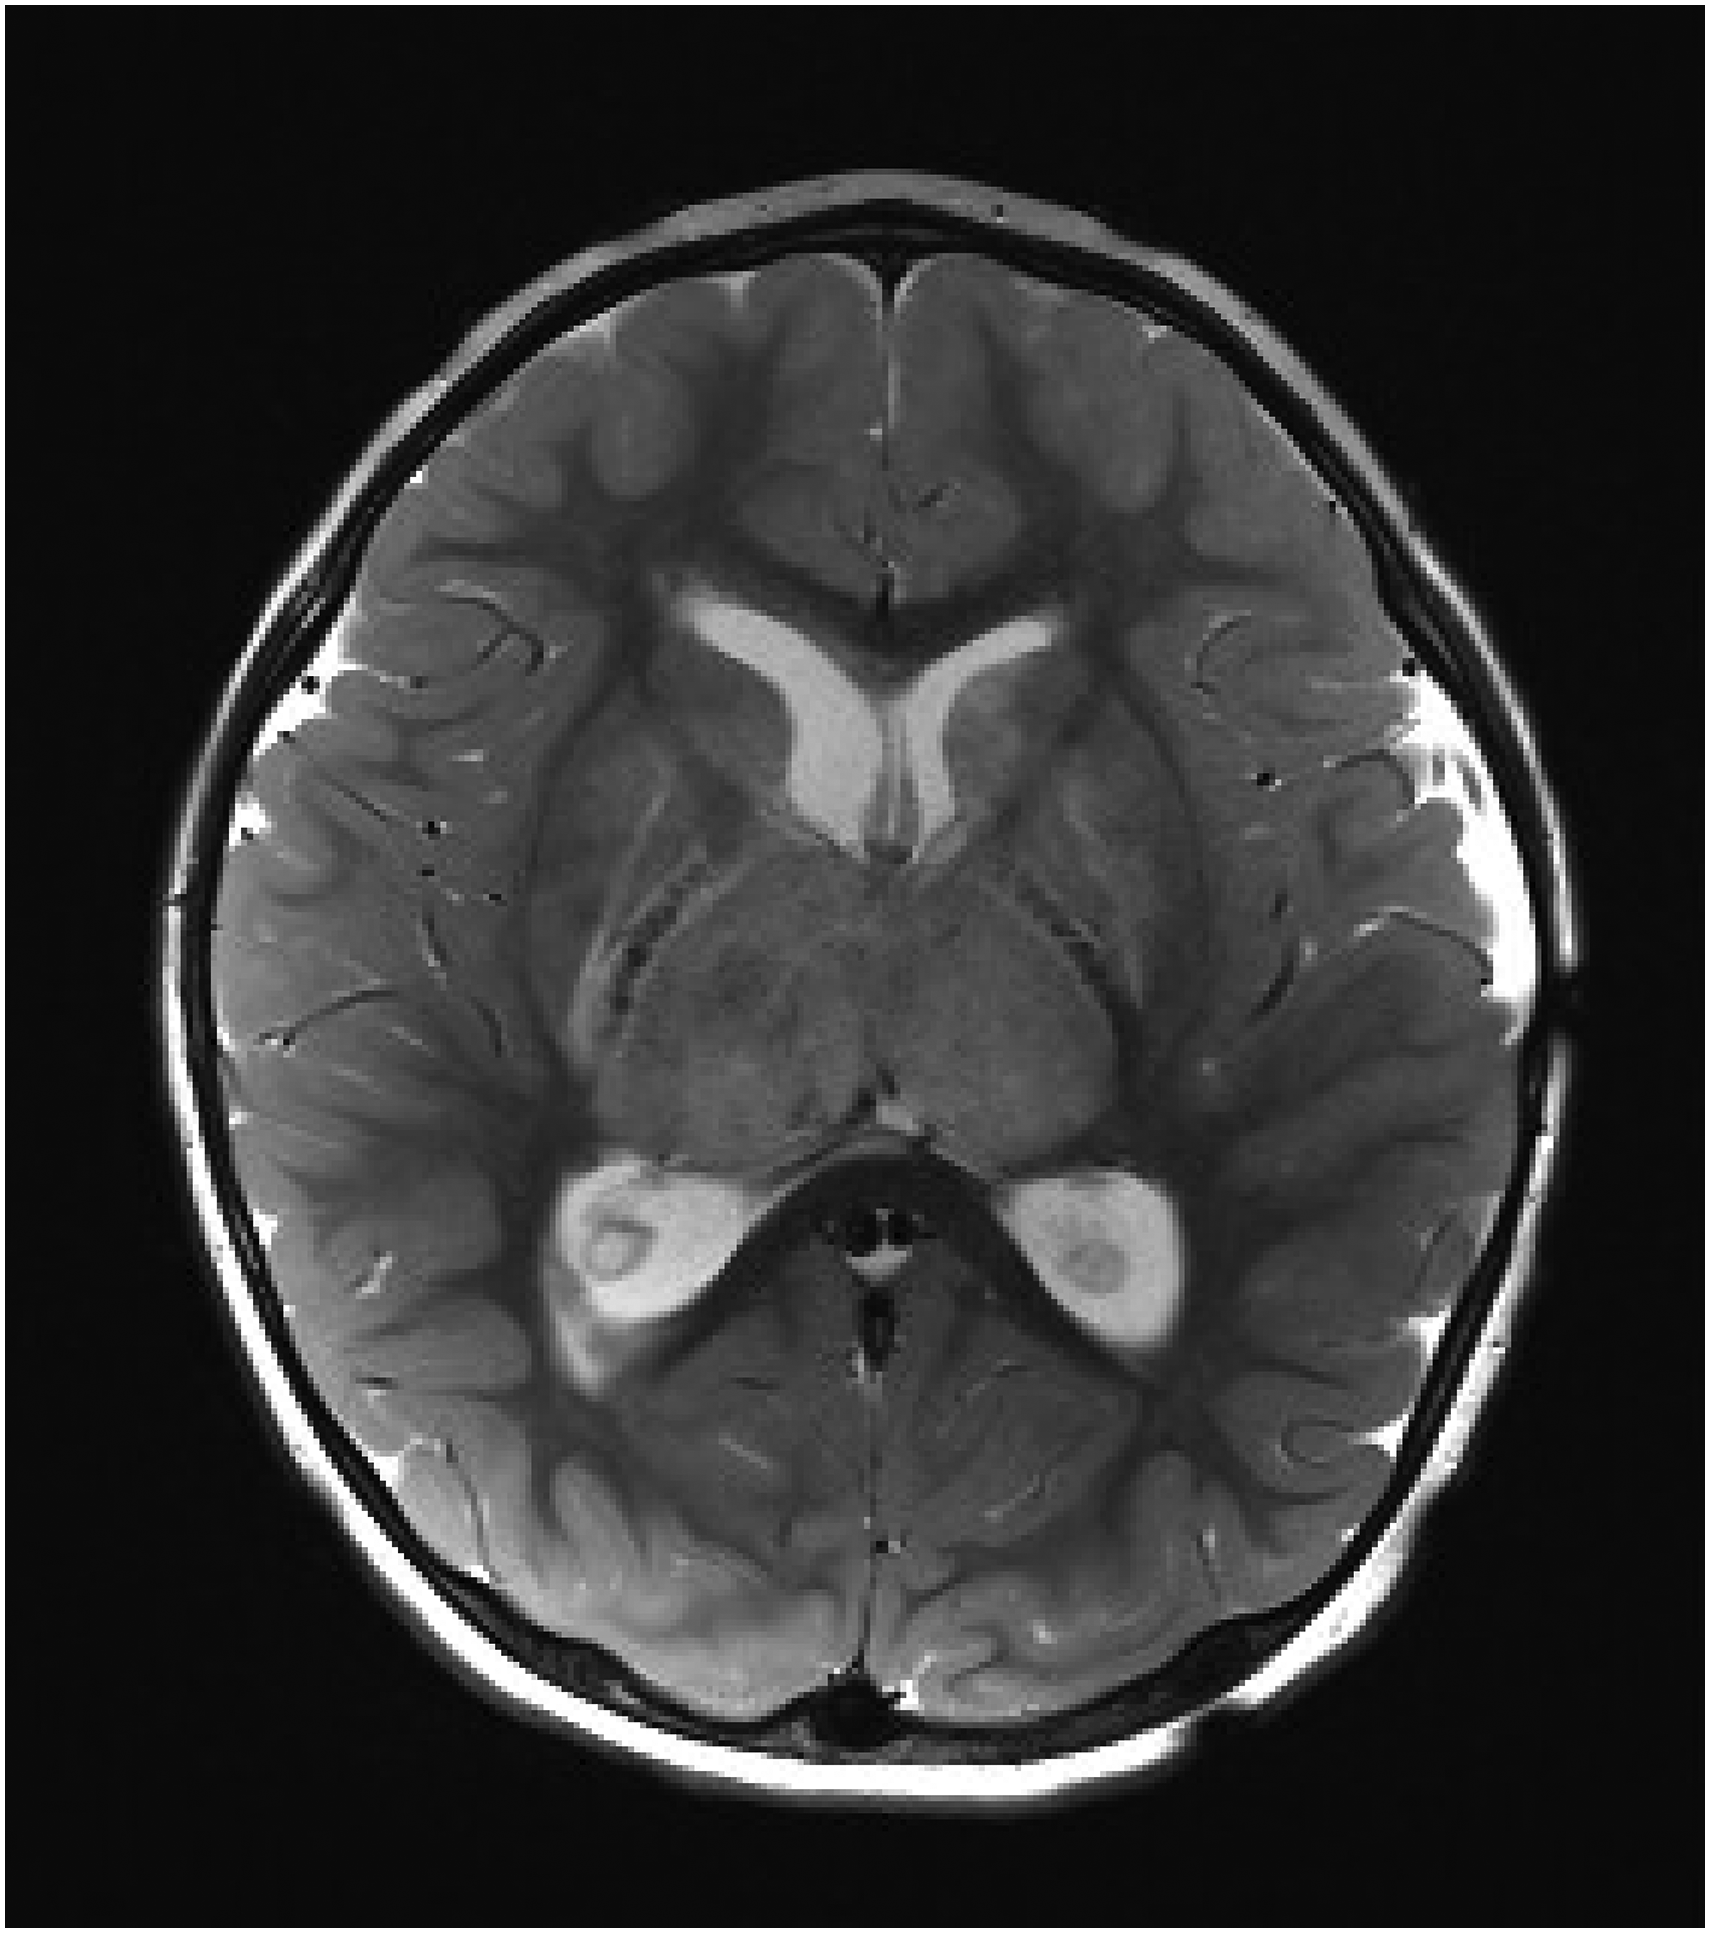

Milk intake ranged from 30 to 80 oz/d. Hemoglobin at presentation ranged from 2.4 to 6.2 (median 4.7) g/dL, platelet count 284 to 924 (median 488) K/mm3, ferritin from 3 to 10 (median 3) ng/mL, and albumin 2.8 to 3.6 (median 3.2) g/dL. The deep venous system was involved in 6 patients, including straight sinus and bilateral internal cerebral vein involvement. Six patients suffered venous infarcts, including thalamic infarcts and deep white matter infarcts (Figure 1). Venous stroke was present in 86% (6/7) of children with cerebral venous sinus thrombosis due to isolated iron deficiency anemia, in contrast to 28% (45/158) of the entire cerebral venous sinus thrombosis cohort.

Axial T2-weighted magnetic resonance imaging (MRI) scan from a 24-month-old female with iron deficiency anemia and cerebral venous sinus thrombosis showing edema due to venous infarcts of the right greater than left thalami and obstructive hydrocephalus at the level of the third ventricle secondary to thalamic swelling.